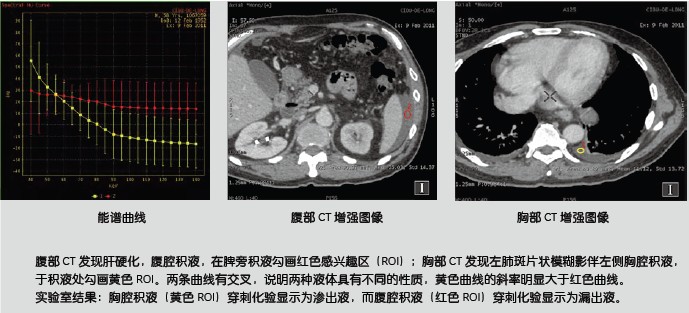

新技術(shù)介紹一:能譜曲線鑒別病灶同源性

能譜曲線體現(xiàn)了不同物質(zhì)對X線的吸收程度,從而體現(xiàn)了物質(zhì)本身的結(jié)構(gòu)特性。從以下的糖水及鹽水的例子可以看出,在常規(guī)CT上表現(xiàn)為同樣CT值-即無法區(qū)分的糖鹽水卻表現(xiàn)為完全不一樣的能譜曲線,從而讓我們可以區(qū)分它們。

同樣,對于常見的胸水的病理類型為滲出液還是漏出液,也可以通過能譜曲線進(jìn)行鑒別。

除以上應(yīng)用之外,能譜曲線還應(yīng)用在鑒別腫瘤原發(fā)灶和轉(zhuǎn)移灶的關(guān)系。